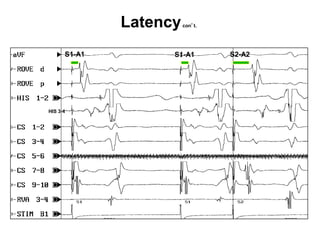

Latency (ARRP)

Latency is defined as the time difference (delay)

between the initiation of a stimulus and the observed

response to that stimulus. As an extra stimulus is

introduced with shorter coupling intervals, the ability

of the targeted tissue to accept and conduct this

impulse becomes more compromised. Increasing the

rate of pacing results in less time for recovery of tissue

(shortening of the action potential). This is especially

true of AV nodal cells.

Latency   con’t.

S1-A1         S1-A1        S2-A2

HIS 3-4